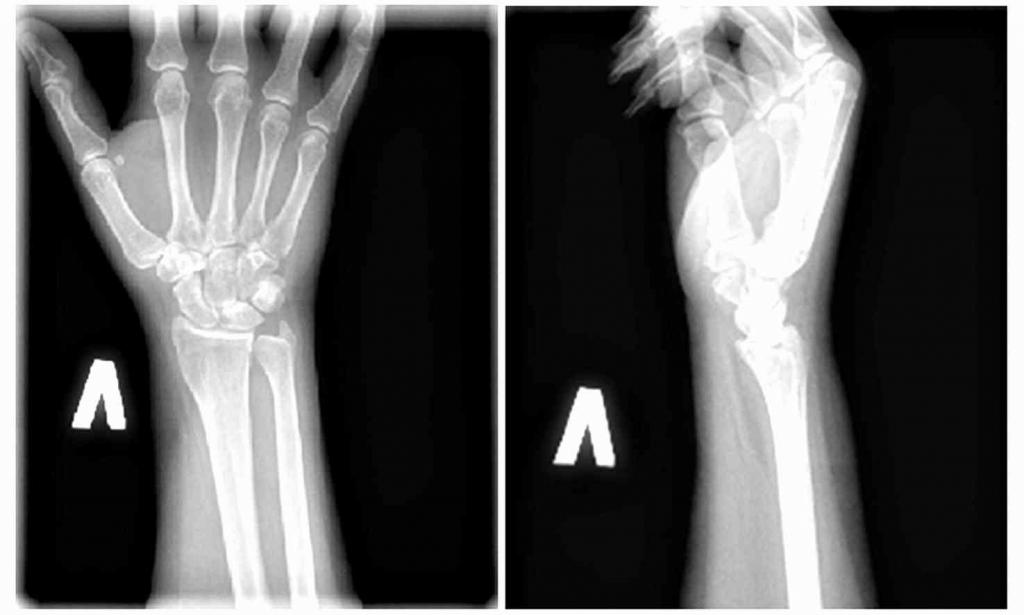

Опытный ревматолог или травматолог может поставить диагноз при первичном осмотре пациента на основании его жалоб и изучения анамнеза. При вялотекущем воспалительном процессе иногда требуется проведение дополнительных исследований:

- рентгенографии;

- компьютерной или магнитно-резонансной томографии;

- ультразвукового исследования.